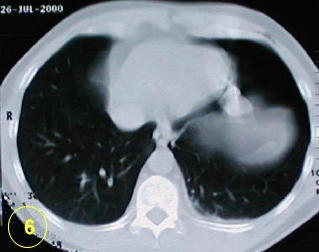

La tomografía computarizada del tórax

y su adecuada interpretación es de gran ayuda diagnóstica

en las patologias del tórax.

Esta forma de presentación de bula

unica, o localizada en un segmento único, de la enfermedad bulosa

pulmonar no es clásica.

Ocacionalmente es difícil diferenciarla

del neumotórax expontáneo.